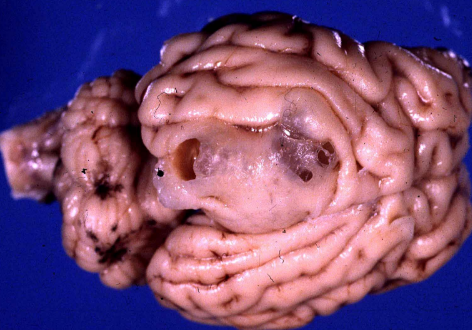

What is this in a goat?

Abscess